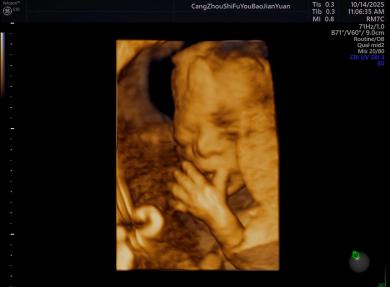

给宝宝的“立体影像”,让产检更安心

科室采用三维/四维超声技术开展胎儿检查,能清晰呈现胎儿面部及身体关键结构的影像,让准父母直观感受宝宝的发育状态。检查中,医生会借助技术对唇腭裂、小下颌等结构异常进行细致观察,同时基于三维容积数据,从多个平面评估胎儿心脏、大脑、脊柱等重要部位,为孕期健康管理提供专业参考。

正常胎儿面部三维照片